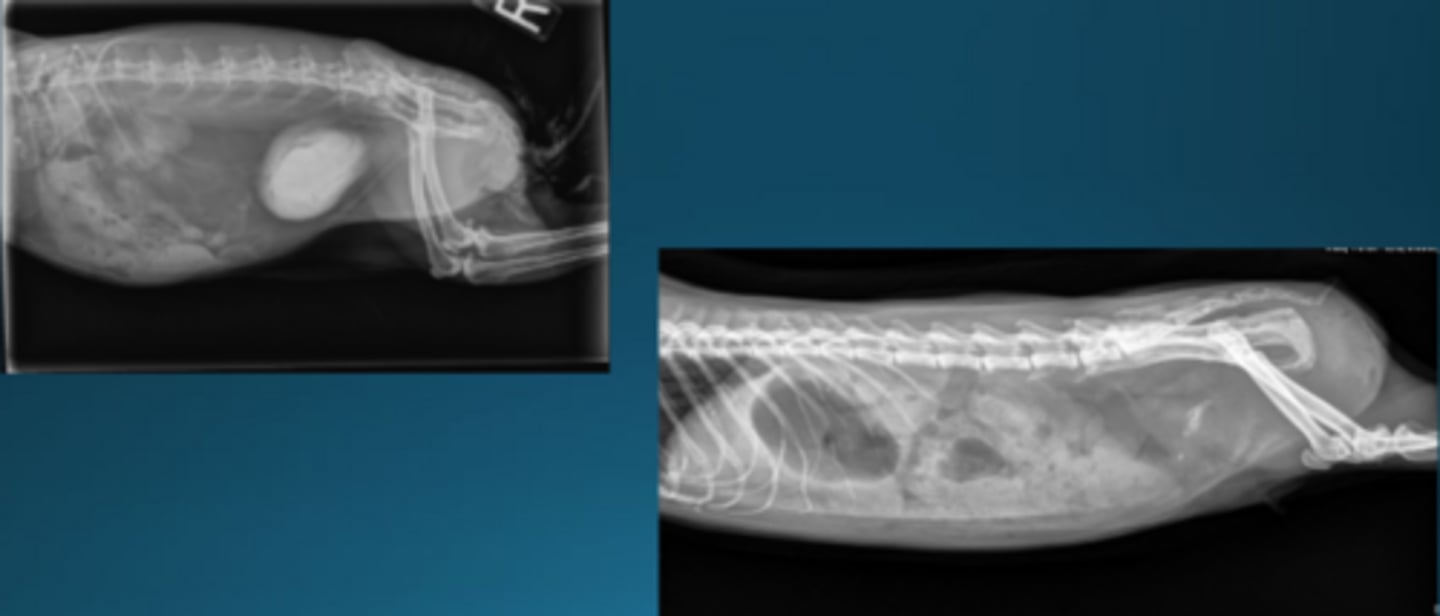

Normal

Is this a normal OR abnormal rabbit?

The caudal border of the stomach should not pass the caudal border of L2

How do you determine if the stomach is normal size on rabbit x-rays?